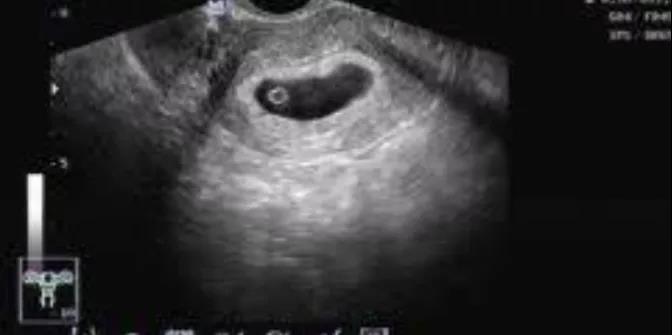

近日,我院接诊了位19岁年轻女性,她在母亲的陪同下,惶恐不安地走进诊室。医生详细问诊后得知,女孩意外怀孕,这次是来做人工流产的。任凭母亲责骂,女孩直流泪不语。